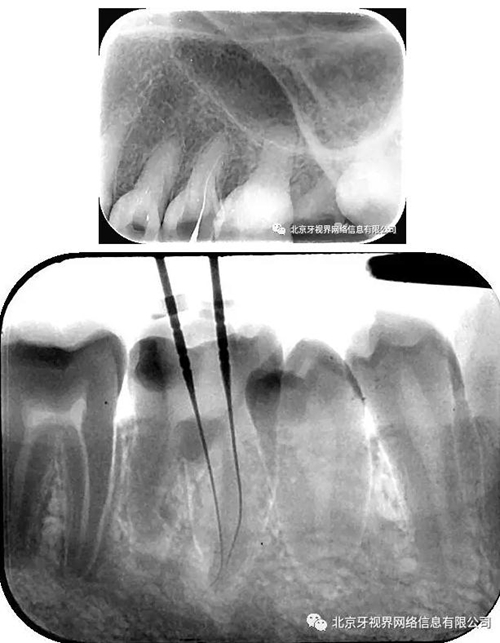

最后附帶近期彎曲根管的圖片

2.如遇彎曲根管,建議多角度拍攝x線片,cbct首選

3.操作中切記盲目下針,遇到阻力后冷靜分析(正向阻力與側(cè)向阻力)后,按其彎曲方向緩慢前行,避免形成新的臺階,很多操作中的難度都是術(shù)者盲目下針,用力過大自己造成的。